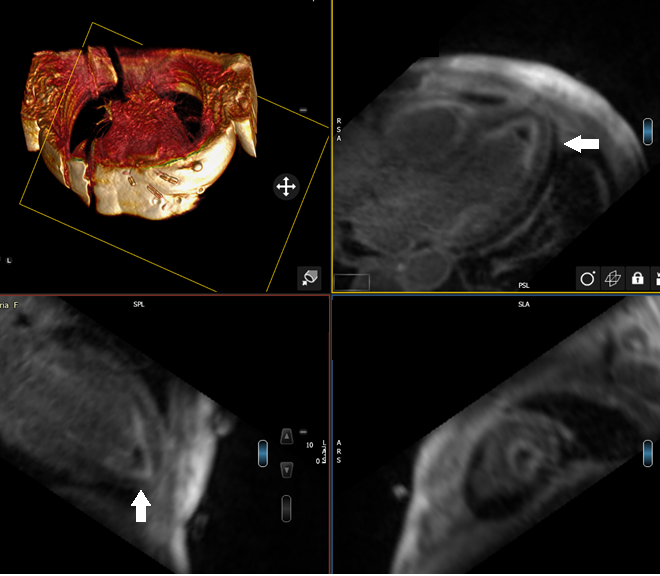

CMR showing a “double V” sign, which includes a normal myocardium, followed by a thickened enhanced endomyocardial layer, and then an overlying apical thrombus. This is a typical finding of Loeffler's endocarditis (Eosinophilic myocarditis). MPR of the 3D LGE images. Evidence of LV apical LGE with an

Long TI confirming biventricular thrombi. Long TI sequence. Evidence of biventricular thrombi that is